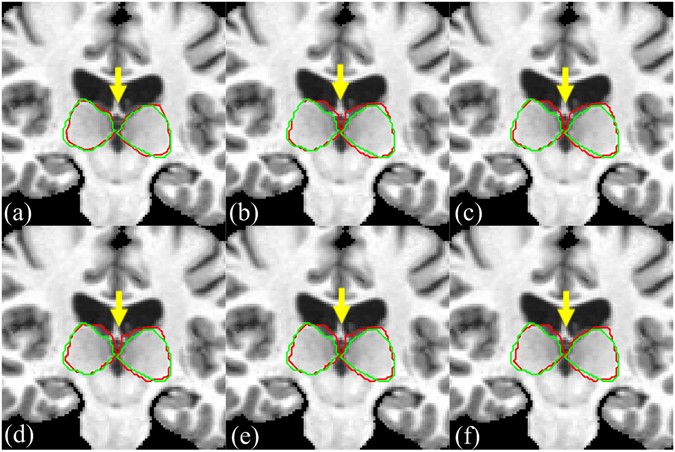

As shown in Fig. 3, ANTS and DRAMMS obviously outperform Demons. The performances of ANTS and DRAMMS are very similar, and it is difficult to evaluate which one is better, even by experts. To avoid possible registration error and to take full advantage of the merit of different registration methods, we combine the ANTS and DRAMMS registration results in a level set framework.

Registration performance comparison between ANTS, DRAMMS and Demons. (a) ANTS, (b) DRAMMS, (c) Demons. Each row represents different patient. The red contours in each column represent the warped thalamus boundary after ANTS, DRAMMS and Demons registration, respectively. The green contours are the ground truth that manually delineated by experts.

For visual comparison, we show in Fig. 7 the segmentation results of MICCAI image No.1006 by our method and five other methods, along with the manual segmentation. It can be observed that the thalamus segmented by our method is more similar to the ground-truth than any other method, e.g., STAPLE, Spatial STAPLE, Major Voting, Weight Voting, and SIMPLE. Particularly, in the region of the yellow arrow, the five other methods cannot locate the left and right thalamus. Our method can correct the registration errors, because the region-scalable fitting (RSF) model in the level set fusion framework can guide the motion of the contour toward the thalamus boundaries.

The segmentation results of MICCAI image No. 1006 by our method and five other methods. (a) Our method, (b) STAPLE, (c) Spatial STAPLE, (d) Major Voting, (e) Weight Voting, (f) SIMPLE. Automatic segmentation results are illustrated in red contour, the manually-delineated thalamus boundary shown by the green contour.